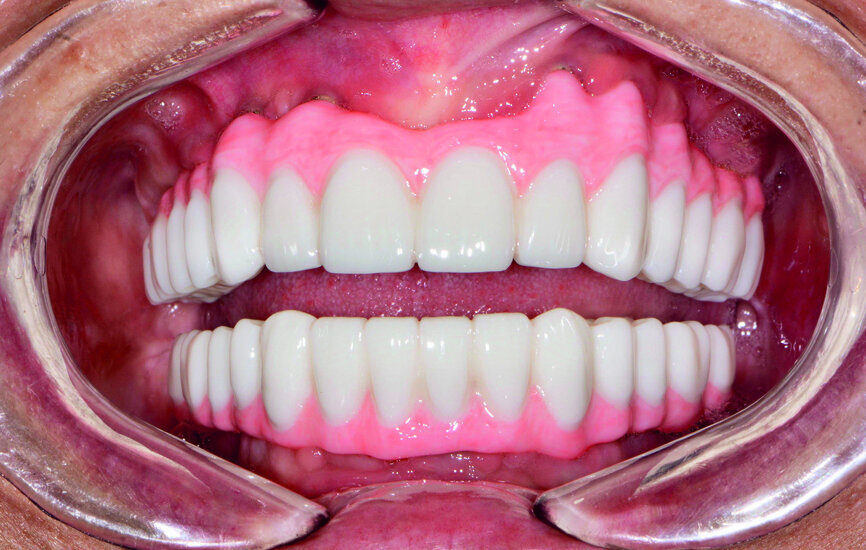

Fig. 21: Post-op retracted open-bite view.

Fig. 22: Post-op retracted closedbite

view.

The final restoration was delivered at the next appointment and established accurate fit, function and interocclusal relationship (Figs. 21 & 22). No adjustments were needed for the monolithic zirconia prostheses because of the PMMA try-in process, which captured the precise modifications needed for proper form and aesthetics. Final radiography confirmed complete seating of the BruxZir restoration on the Inclusive Custom Implant Abutments. The patient was extremely happy with the reconstruction of her maxillary and mandibular arches, which restored aesthetics, dental function, comfort and confidence.